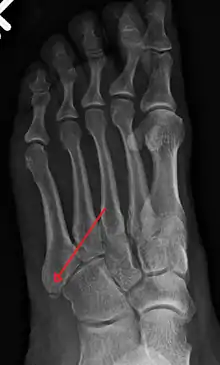

X-ray of foot.